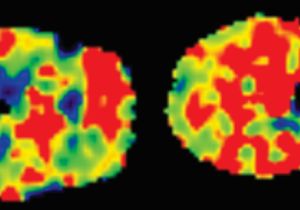

Tens of millions of Americans will suffer at some point in their lifetime from obsessive-compulsive disorder. Functional MRI might help doctors predict who responds best to one of the most common treatments.